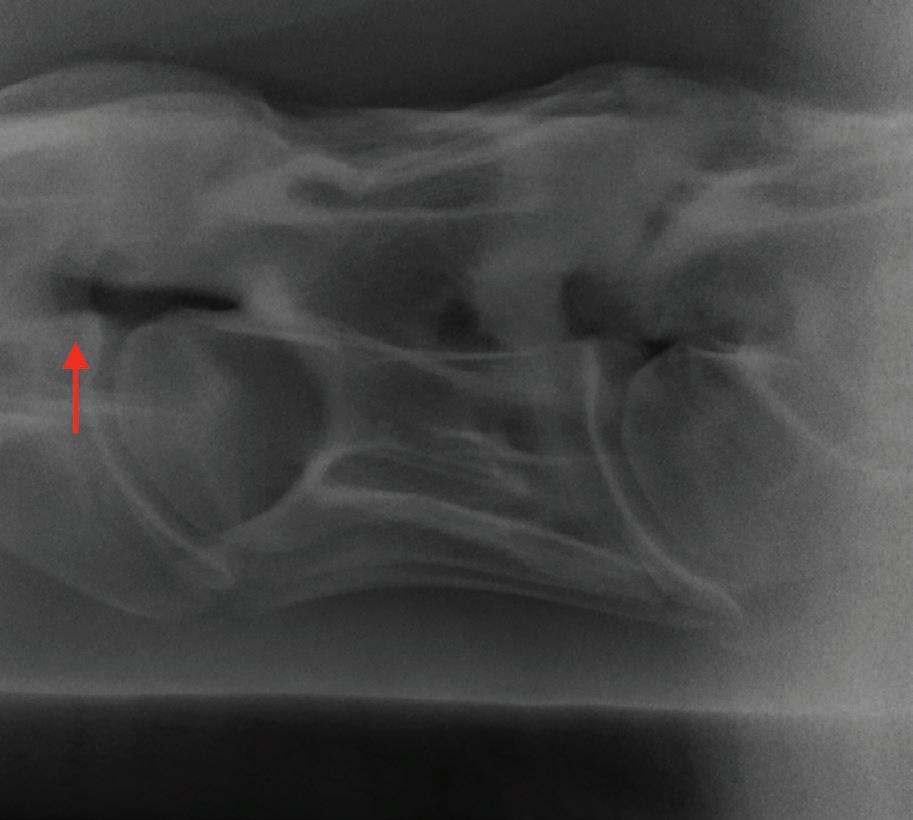

Sex: Gelding

Weight: 563 kg

PRESENTATION

The horse was presented to our hospital on 24 January 2020. The owner reported that the horse was normal before going to the breakers for 5 weeks to begin its education. When arriving home, the horse was immediately noted to have a hind limb problem (when circling), with a swollen left hind leg. Since this time, intermittent abnormalities were suspected by the owner. The owner noted that the horse had lost weight since being at the breakers.

INITIAL DIAGNOSTICS

Neurological examination

A neurological examination can be divided into four sections2:

1. Evaluation of mental status (observing the horse from a distance e.g. in a stable or yard)